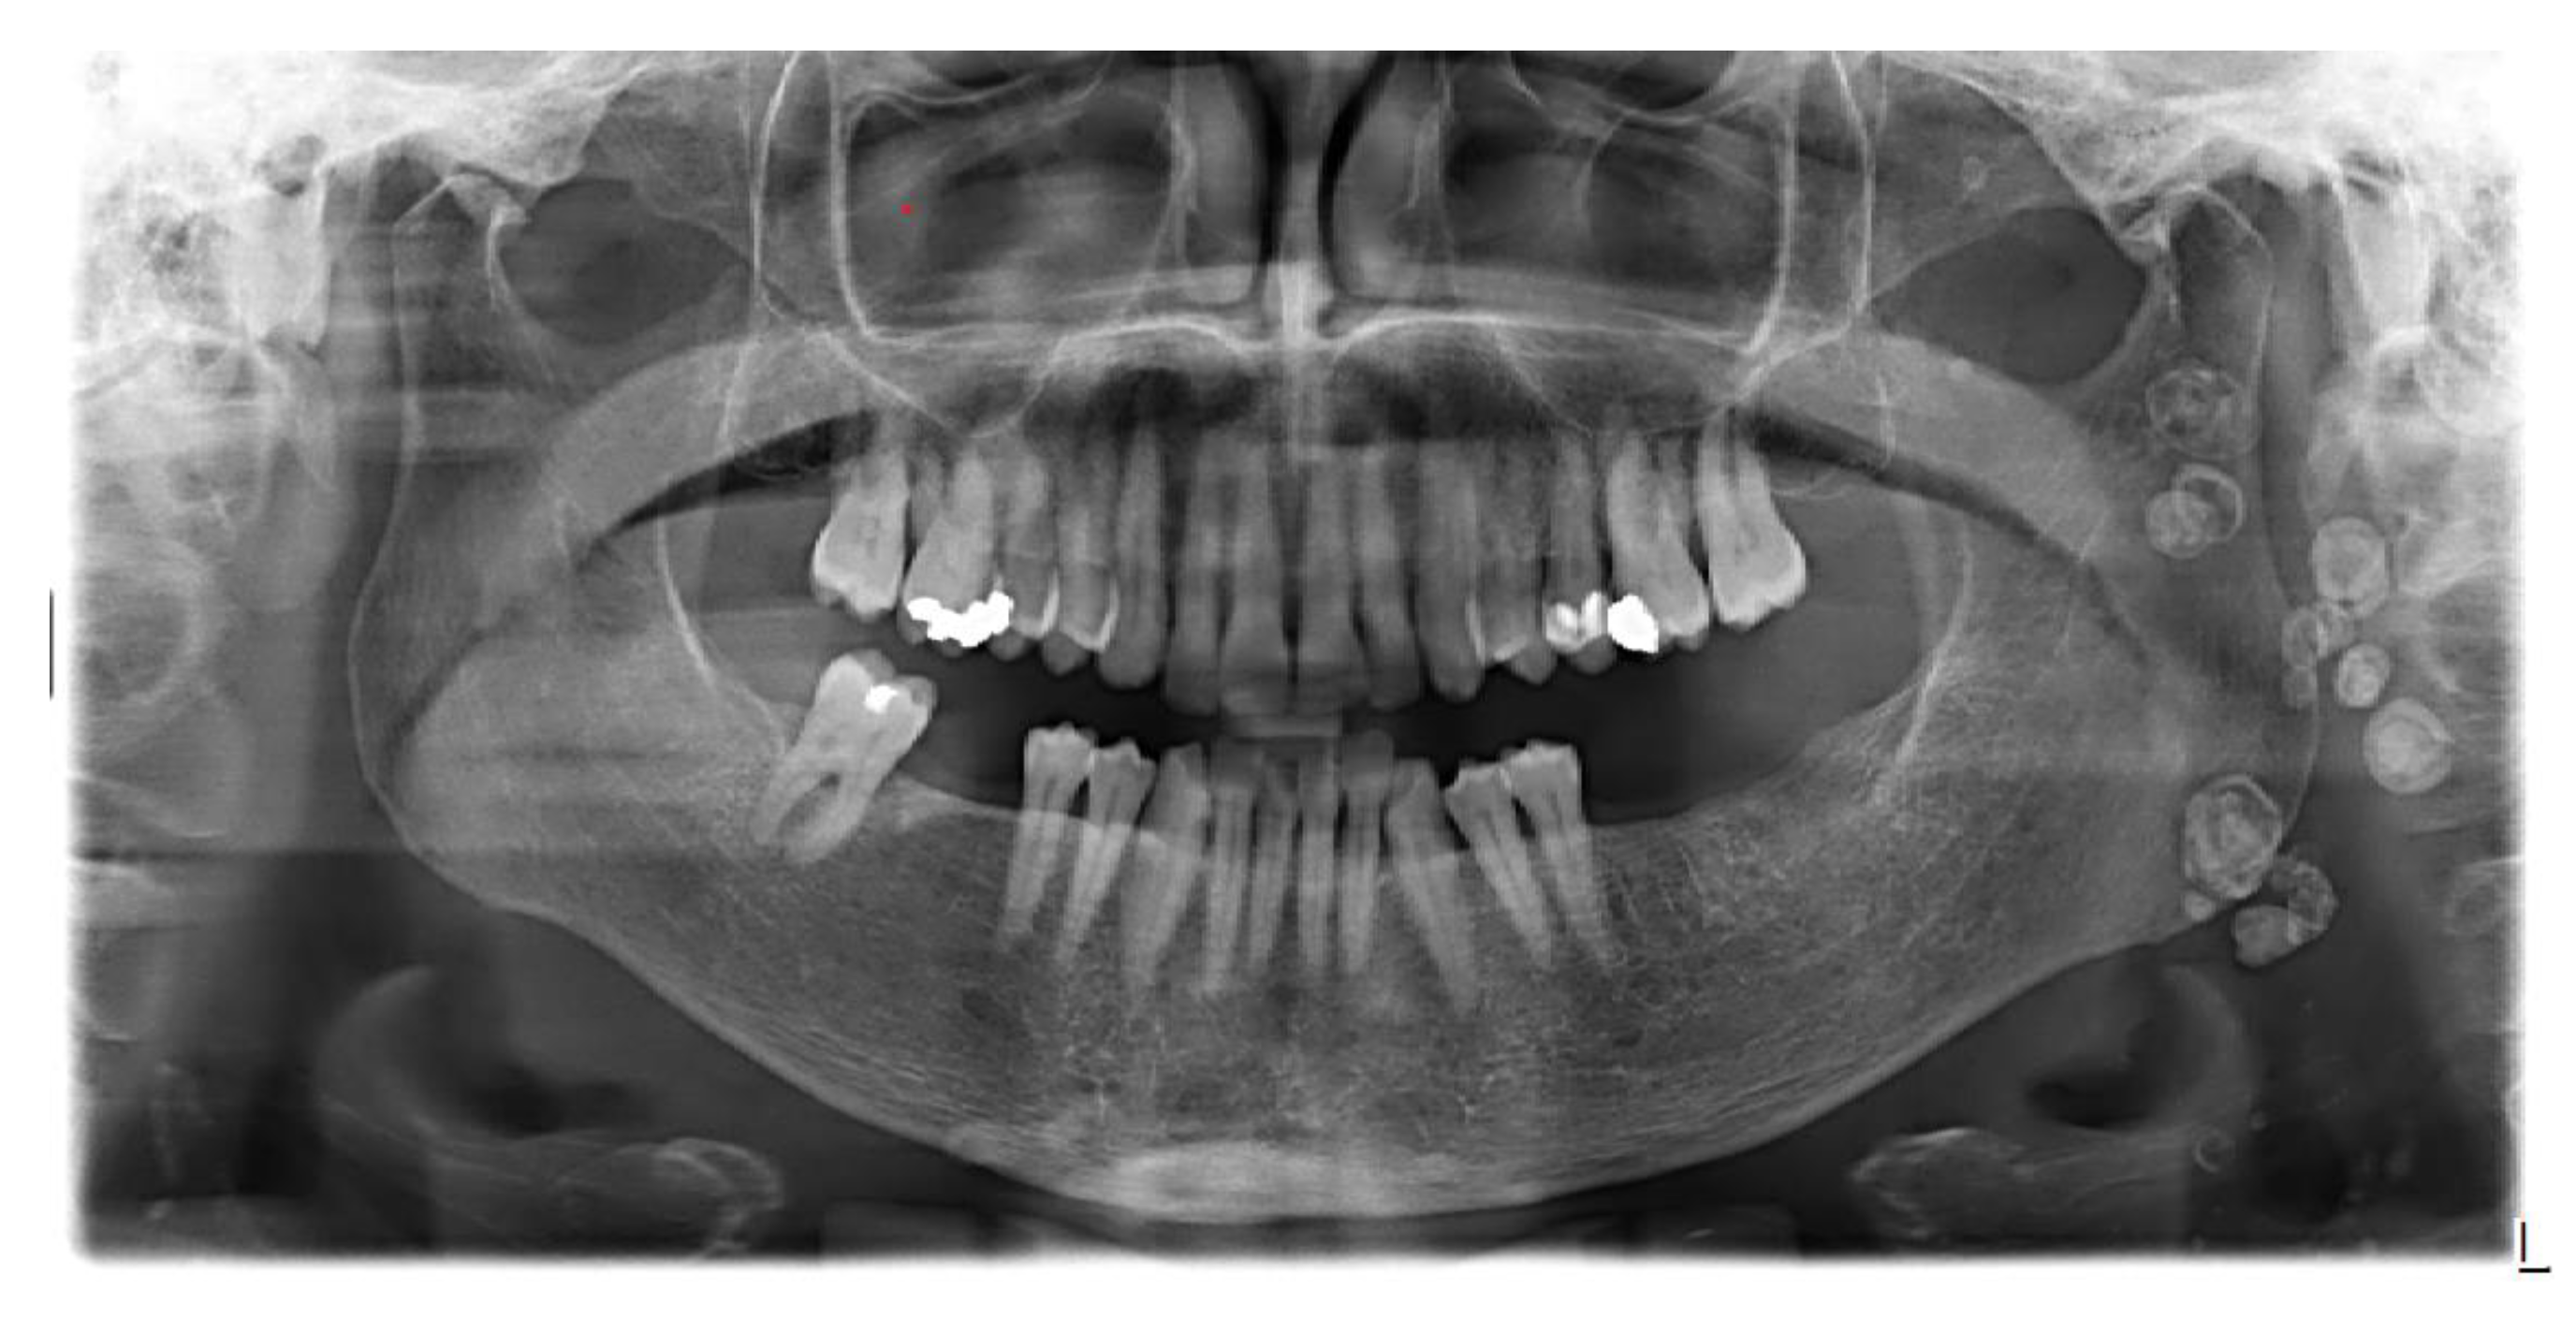

2. Case Presentation